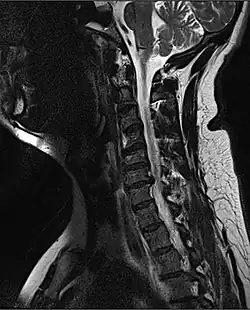

| MRI of a fractured and dislocated cervical vertebra (C4) in the neck that is compressing the spinal cord | |

A radiographic evaluation using an X-ray, CT scan, or MRI can determine if there is damage to the spinal column and where it is located.[10] X-rays are commonly available[89] and can detect instability or misalignment of the spinal column, but do not give very detailed images and can miss injuries to the spinal cord or displacement of ligaments or disks that do not have accompanying spinal column damage.[10] Thus when X-ray findings are normal but SCI is still suspected due to pain or SCI symptoms, CT or MRI scans are used.[89] CT gives greater detail than X-rays, but exposes the patient to more radiation,[91] and it still does not give images of the spinal cord or ligaments; MRI shows body structures in the greatest detail.[10] Thus it is the standard for anyone who has neurological deficits found in SCI or is thought to have an unstable spinal column injury.[92]